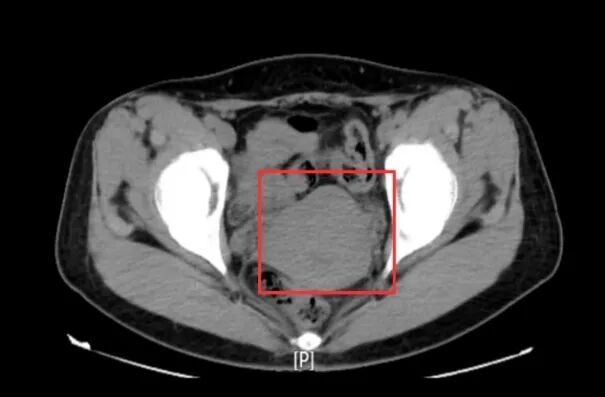

近日,一名宫颈肌瘤病史多年,要求微创手术剥除宫颈肌瘤的患者慕名来到我院妇科主任邵莉萍的专家门诊求医,她只有一个要求保留子宫…… 这位患者46岁,来我院之前已辗转多家医院,均建议切除子宫,但患者强烈要求保留子宫,故迟迟未能接受诊疗。 子宫肌瘤是女性生殖器最常见的良性肿瘤,发生于20%~40%的生育期妇女,按其生长部位可分为宫体肌瘤和宫颈肌瘤,其中宫颈肌瘤约占10%左右。宫颈肌瘤是生长在子宫颈上的肌瘤,病因主要与雌孕激素水平的增高有关。其前方与膀胱、后方与直肠、两侧与输尿管及子宫动脉关系密切,因其特殊的解剖位置,宫颈增大变形,常引起盆壁间手术操作间隙变窄,宫颈、输尿管及子宫动脉间的解剖结构发生改变,因而手术操作困难,通常采用传统的开腹手术,且多以子宫切除作为治疗宫颈肌瘤治疗的首选,很多年轻患者因此失去了宝贵的子宫。 患者入院后,邵主任带领团队结合患者病史、查体及影像检查等资料制定了周密的手术方案——宫腹腔镜联合手术剥除宫颈肌瘤。近年来,随着妇科腔镜技术的迅猛发展,宫颈肌瘤已不再是腹腔镜手术的禁忌,但腹腔镜下宫颈肌瘤剥除术对术者操作水平要求极高,如果没有认清解剖关系,没有下推膀胱或游离出输尿管,没有充分暴露术野,很可能出现膀胱、肠管及输尿管的副损伤或者导致术中术后大量出血、手术时间延长等不良事件,术者的操作技巧、手术经验及止血、缝合技术是手术成功的关键。 经过充分的术前准备,手术如期开展。邵主任带领妇科团队宫腔镜下探查宫颈肌瘤未凸向宫腔,腹腔镜探查宫颈前壁肌瘤。打开膀胱反折腹膜,下推膀胱,防止损伤膀胱。横切口打开肌瘤的包膜,在包膜内进行操作,减少临近组织及重要结构的损伤。剔除肌瘤后缝合止血,然后再次宫腔镜检查宫颈管形态如常。另外,术中发现子宫内膜息肉一枚、宫颈管粘膜下肌瘤一枚,一并予以切除,手术顺利,出血量极少,目前患者现已康复出院。 患者每一次坚定的选择,都是医院前进的动力。医护团队每一次成功的手术,都是患者选择的底气。双向奔赴的信任里,每一声谢谢,每一句放心,都是流淌在医患间的暖流。我院妇科团队熟练开展宫腹腔镜联合手术、宫腔镜子宫病损切除、宫腔镜子宫内异物取出等先进技术,为广大女性健康保驾护航。 |